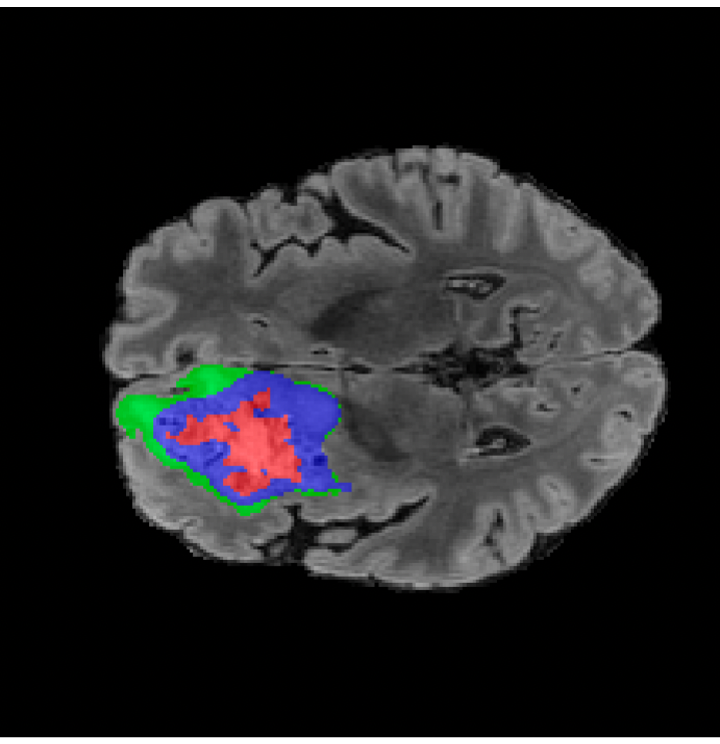

Tumour Information Preservation. For the brain tumor segmentation, we use a Swin UNETR model[28, 70], trained with random rotation, and intensity as data augmentation. On the test set with human ground-truth annotations (), the brain volumes generated from single slice input preserve the volume of the different tumour components (paired t-test, for all 3 classes). In Figure 4, we highlight the tumor profiles of the generated MRIs compared to the ground truth tumour profile. The real MRI Dice score in the test set is 85.15 while the generated MRIs from a single slice have a dice score of 83.09. This shows how the generated MRIs indeed preserve the tumor information and can act as an affordable and informative pseudo-MRI, before conducting an actual costly MRI examination in hospitals. More detailed results are provided in supplementary material.

On the test set with human ground-truth annotations (), the brain volumes generated from single slice input preserve the volume of the different tumour components (paired t-test, for all 3 classes) (see Table I). The real MRI Dice scores are put for reference to our generated MRIs. X-Diffusion outperforms baselines TPDM [39] and ScoreMRI [19] in tumour preservation (see Table I and Figure III). We ran experiments comparing the tumour segmentation Dice Score varying X-Diffusion configurations. The multi-slice input X-Diffusion achieves marginally better Dice Score than the single slice input model (83.47 83.09). We also ran experiments with slice input used for volume reconstruction intersecting or not with tumour. We observe on average a drop of 6% Dice Score (see Table I). Further away from the tumour the input slice for volume reconstruction is selected, we observe a linear decrease in tumour segmentation Dice Score with lowest value of 77.21 Dice Score (see Figure VI).